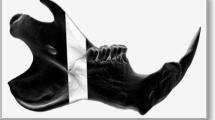

After the macroscopy analysis, the tibiae were analyzed in a three-point bending test until failure, using the universal-testing machine (EMIC DL 2000, EMIC Equipamentos e Sistemas de Ensaio Ltda, São José dos Pinhais, Brazil). Each specimen was positioned horizontally on the two holding fixtures with a distance of 16 mm on the machine, while the upper loading fixture applied the force to the middle of the diaphysis at a loading of 20 N at 1.0 mm/min displacement (Fig. 3a). Load and displacement data were recorded and subsequently, load vs. displacement curves were plotted. Evaluations were derived from data with flexural strength (N/mJ) and stiffness values (N/mm). The fractured tibiae (Fig. 3b) were maintained, after the mechanical test, in phosphate buffered saline until the attenuated total reflectance Fourier transform infrared spectroscopy (ATR-FTIR) analysis.